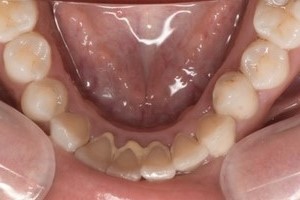

Before①

Before②

| 主訴 | 下顎 歯石除去したい |

| 治療内容 | スケーリング |

| 治療期間 | 30分 |

| 治療費 | 約1,500円(保険診療) |

| リスク・副作用 | 知覚過敏、歯肉退縮 |

| 治療方針 | 歯肉縁上歯石を除去してから歯肉縁下歯石を除去します。ご自身でのプラークコントロールができるようになったら定期検診に移行します。 |

| 担当者所見 | 半年ぶりの歯科医院の受診。歯石が付きやすいためセルフケアの重要性をお伝えして、定期的にクリーニングを行います。出血率が高く炎症が強いため、今後はセルフケアを強化して歯周病治療を行います。 |